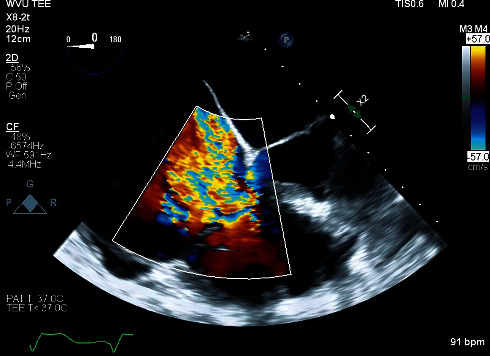

开发无铅心脏起搏器是为了减少与传统经静脉起搏器相关的并发症。虽然这项技术仍然相对较新,但植入的设备越来越多。使用这些装置的患者的围手术期管理一直被低估;因此,我们试图增加有限的知识体的围手术期管理的患者无铅心脏起搏器。一位老年女性患者,因心动过速-心动过缓综合征伴有间歇性完全性心脏传导阻滞,使用Micra VR经导管起搏系统无铅心脏起搏器,因严重三尖瓣返流,计划进行选择性三尖瓣置换术。根据电生理学家的时间安排,在手术前几小时进行起搏器检查;该设备保持在其编程的VVIR模式,并且预期即将进行的手术,基本频率从每分钟60次增加到每分钟80次。在术前评估时,麻醉师要求电生理小组在术中待命,因为担心在起搏器依赖的情况下过度敏感和/或心率反应性起搏可能发生不良的心动过速。外科医生在心脏手术期间使用单极电。尽管患者术前在重症监护病房有起搏器依赖的证据,但术中心电图和动脉内侵入性监测未发现电磁干扰导致过感或速率调节。关于无导线心脏起搏器围手术期管理的循证指南尚不存在。随着这些设备变得越来越普遍,进一步的评估将至关重要,以确定现有的指导方针是否适用于传统经静脉起搏器的围手术期管理。

Leadless cardiac pacemakers were developed to reduce complications associated with conventional transvenous pacemakers. While this technology is still relatively new, devices are increasingly being implanted. The perioperative management of patients with these devices has been underreported; we thus seek to add to the limited body of knowledge of perioperative management of patients with leadless cardiac pacemakers. An elderly female patient with a Micra VR transcatheter pacing system leadless cardiac pacemaker placed for tachycardia-bradycardia syndrome with intermittent complete heart block was scheduled for elective tricuspid valve replacement for severe tricuspid regurgitation. Pacemaker interrogation was performed several hours prior to the scheduled surgery based on the electrophysiologist's availability; the device was kept in its programmed VVIR mode, and the base rate was increased from 60 to 80 beats per minute in anticipation of the upcoming surgery. Upon preoperative evaluation, the anesthesiologist asked that the electrophysiology team be placed on standby intraoperatively due to the concern that either oversensing in the setting of pacemaker dependence and/or undesirable tachycardia from rate-responsive pacing could occur. The surgeon used monopolar electrocautery for the duration of the cardiac surgery. Despite the patient having evidence of pacemaker dependence in the intensive care unit preoperatively, no electromagnetic interference leading to oversensing nor rate modulation was detected during intraoperative electrocardiographic and intraarterial invasive monitoring. Evidence-based guidelines regarding perioperative management specifically of leadless cardiac pacemakers do not exist. As these devices become more prevalent, further evaluation will be paramount to determine whether existing guidelines for perioperative management of conventional transvenous pacemakers apply.